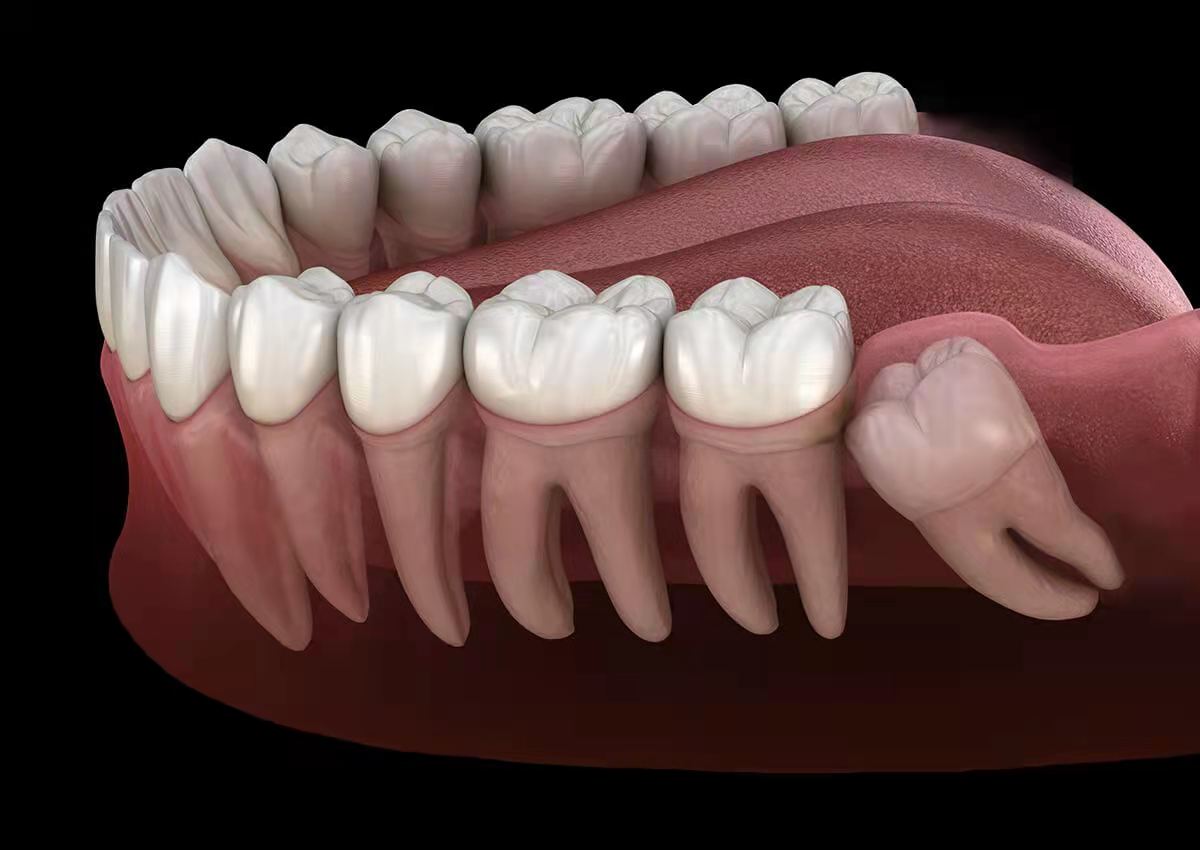

③影响其他牙齿

智齿在出现过程中,经常会影响到周围的牙齿,甚至会把周围本来好好的牙齿给顶坏了,这个时候也必须拔除。